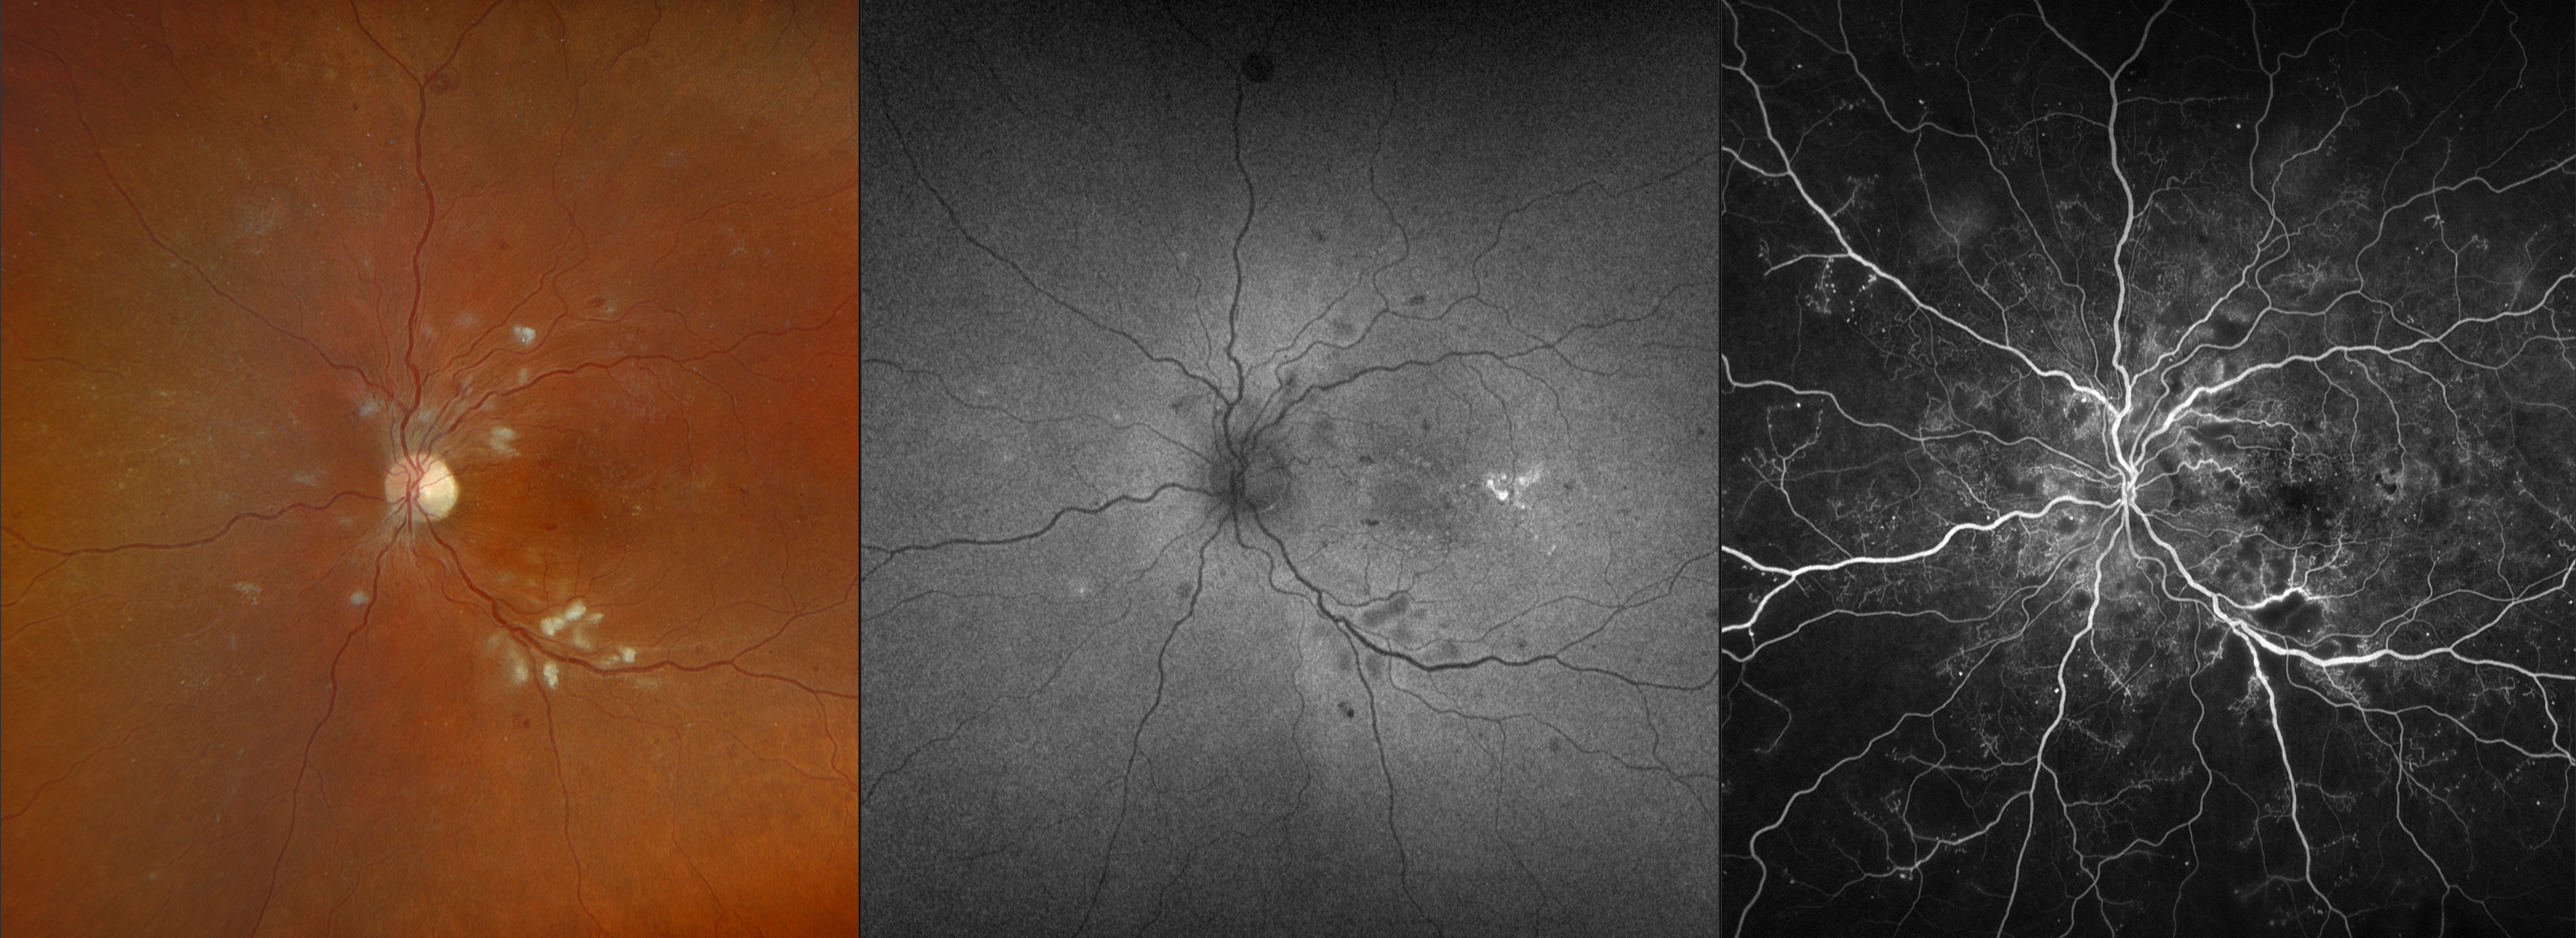

Proliferative Diabetic Retinopathy Presented by Jody Troyer, CRA This photograph received Honorable Mention, Cross Categories in the 2025 OPS Scientific Exhibit. Filed Under Retina OPS Photo